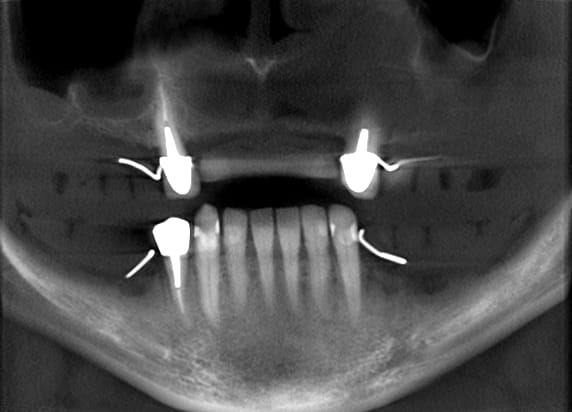

> Patient trop engagé ds la mentonnière donne ce genre de rétrécissement

> mésio-distal ds la zone antérieur

Au maxillaire il faut faire une implanto totale et stt ne pas garder les canines

A la mandibule faut disker mais ça va

PS il faut d abord faire réaliser des modèles stéréolithographiques par Materialise pour se prononcer au final

Mais c est un joli cas ;-)))))))))